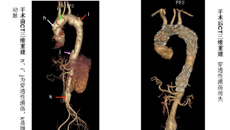

2013年5月23日,一附院外七科为一例主动脉多发性穿透性溃疡、腹主动脉瘤、高血压病、高血脂、冠心病的患者实施腔内覆膜支架植入术,患者于术后10天康复出院。陈先生感动不已,万分感谢。 大血管外科是踏着鲜血走出来的,随着大血管腔内治疗的出现,大血管疾病的死亡明显下降。但仍然把升主动脉和主动脉弓的血管腔内治疗一直视为相对的禁忌。主动脉穿透性溃疡、主动脉夹层、主动脉瘤破裂及主动脉壁间血肿被称为主动脉急性综合...06.102013